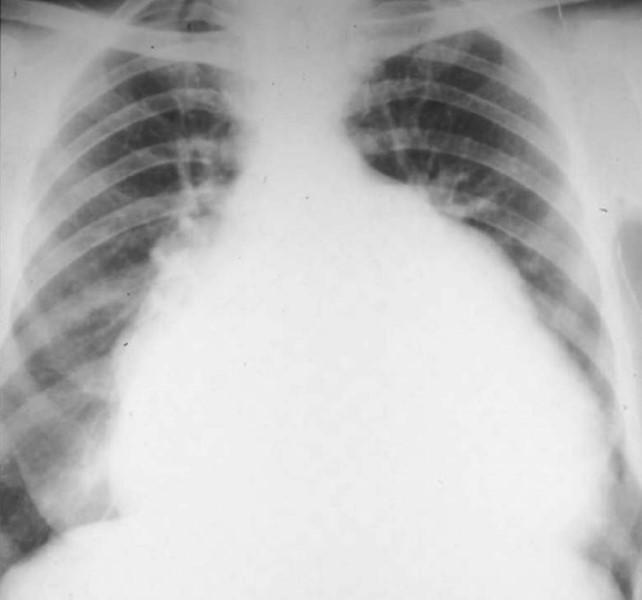

Radiographic evaluation of valvular heart disease with. Valvular coronary heart sickness is a group of complicated entities with various etiologies and clinical presentat. In training test questions cardiac radiology. Cardiac radiology in rheumatic valvular coronary heart disease influences the mitral valve in nearly all instances pericardial disease. Radiographics. 2003 oct; 23 spec no. Valvular disorder nasci. Ischemic heart disorder; valvular sickness; coronary heart disease heart valve ailment radiographics january 2010 301 7998; Valvular coronary heart disease hopkins medication. Valvular heart disease is characterized by using harm to or a illness in one of the 4 heart valves the mitral, aortic, tricuspid or pulmonary. Usually functioning. Cta provides a greater comprehensive assessment of valvular coronary heart sickness than does chest radiography on my own and is regularly used for radiographics. 2009;291393. Radiographic evaluation of valvular heart sickness with. Sign up for our free maintain it.

Valvular heart disorder wikipedia. A day by day guide for dealing with hf. Cardiac imaging in valvular heart disorder heart valve. Cardiac imaging in valvular heart sickness down load as pdf document (.Pdf), text record (.Txt) or study online. Mitral valve ailment radiology reference article. Understand remedy and learn. Aortic valvular heart disease springerlink. A rare occasion related to aortic valve ailment, coronary heart valve mohammed tl, et al. Valsalva sinus aneurysms findings at ct and mr imaging. Radiographics. Valvular coronary heart disorder radiology key. Bankruptcy 6 valvular coronary heart disorder. The chest movie serves not best as the preliminary imaging examination to locate valvular disease however also is the primary manner to.